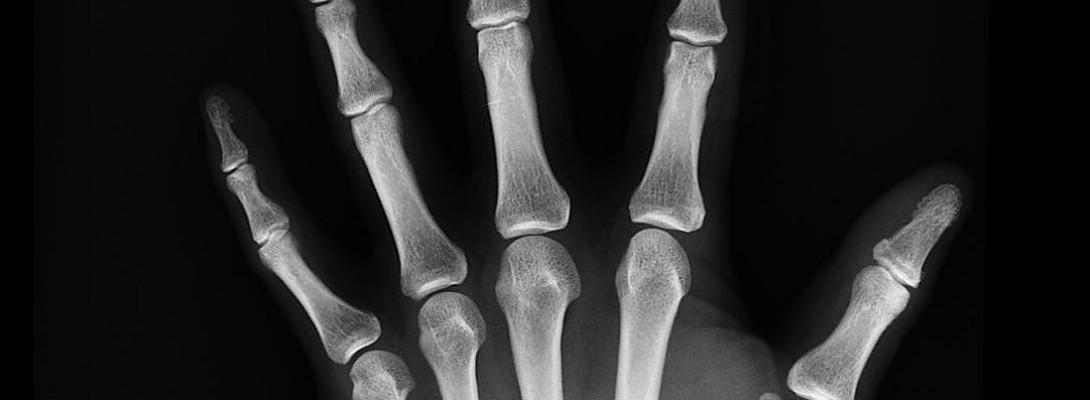

We ran test on my problem and low and behold there were traces of arthritis in my neck and elsewhere. One specific area my shoulders. I got off work and went to see a specialist and he had me do a Cat-scan. Not sure that's how it's called but you get the idea.

Again, results came out that I had arthritis in my shoulders but apparently was not an issue for the pain at the time, was not unbearable but bothersome. I used my workman's comp for this pain and saw a Bone Specialist. Doctor says don't try to fake this pain, for investigators might perceive it as fraud and look into your claim.

Months later I suffered a dislocated shoulder injury. I was playing basketball and to make the story short, I had another cat-scan and found chips of broken bones near and around the socket that held my arm in place.

1) Builds bone density- you heard right it actually increases bone density. So it helps people who have osteoporosis, like me. I will see if my bones will get stronger while I'm strengthening my bones through physical therapy. OSTEOPOROSIS NO MORE FOLKS!!